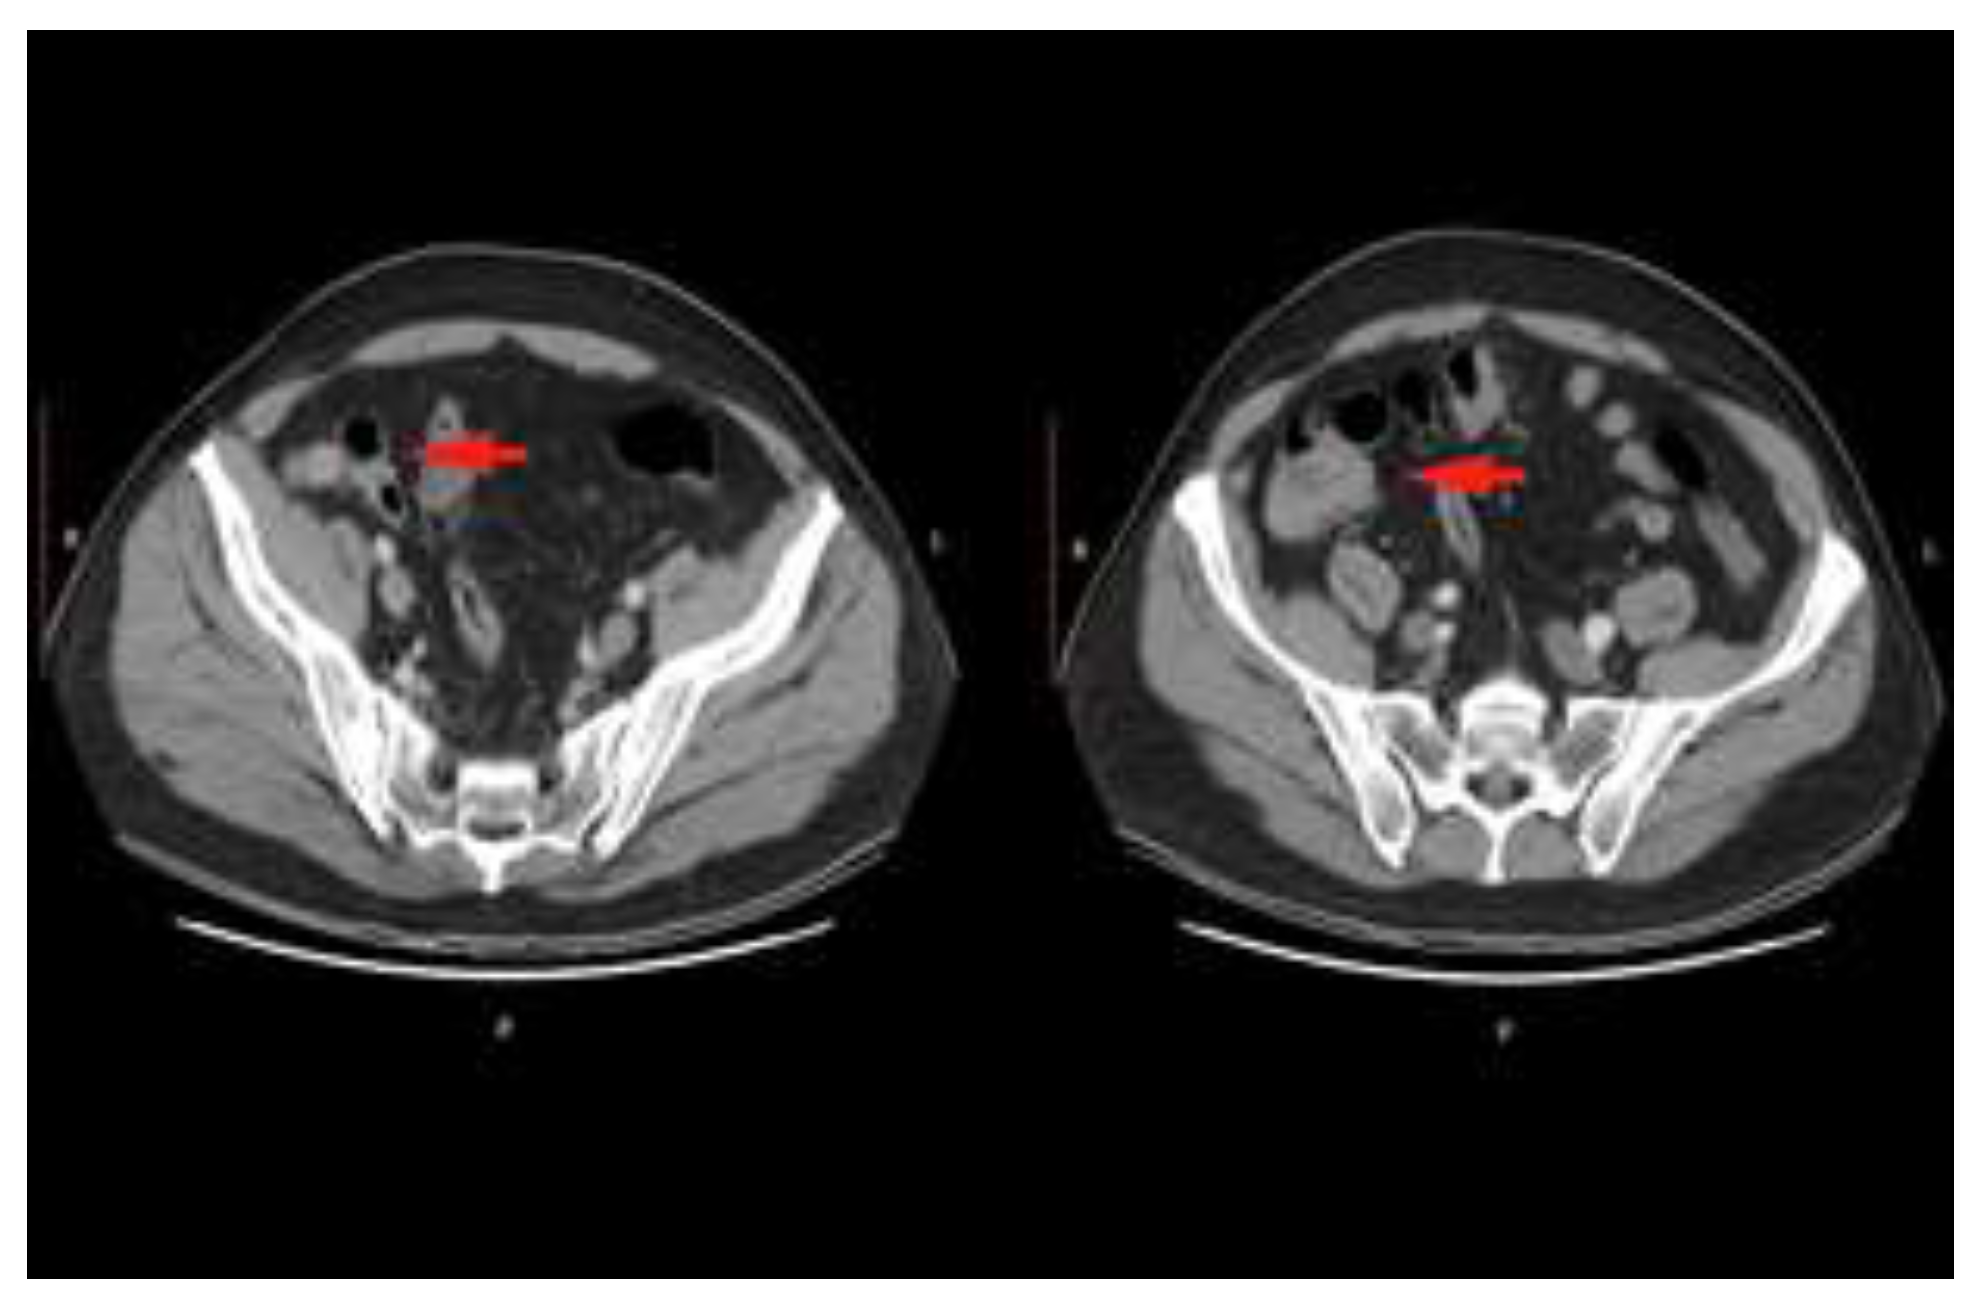

Case presentation